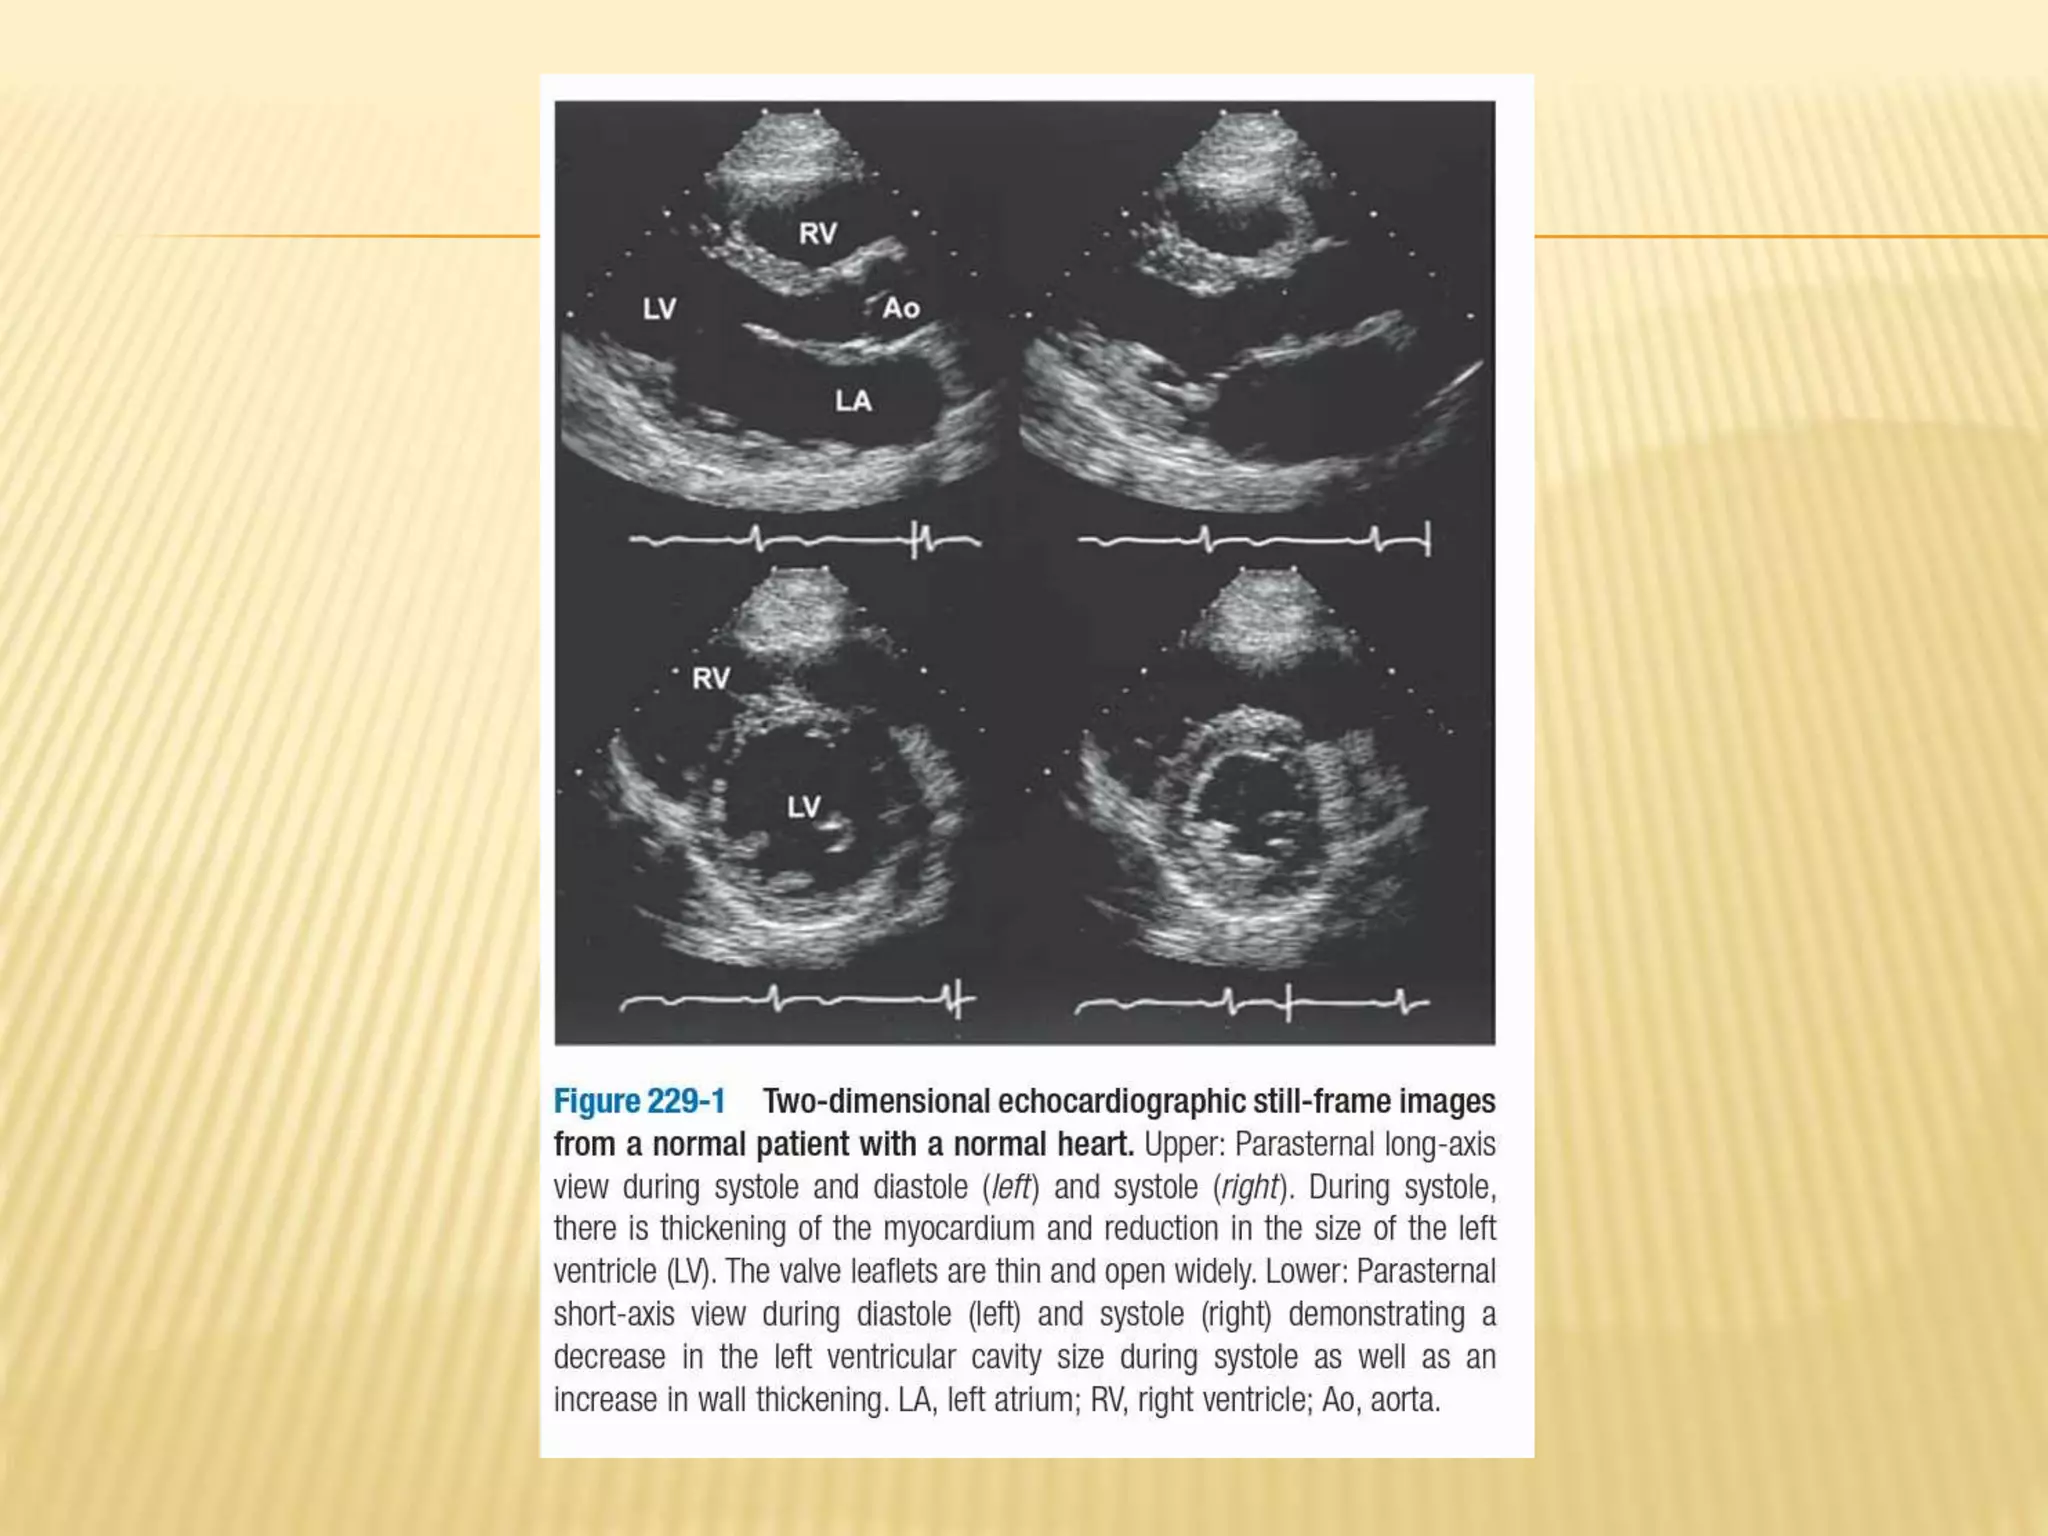

2D ECHOCARDIOGRAPHY

 Principle-ultrasound reflection off cardiac

structures to produce images of heart.

 For TTE (transthoracic ) echocardiogram,

imaging is performed with a handheld

transducer placed directly on chest wall

 Advantage – instantaneous images of

cardiac structures is obtained for

interpretation

 Ideal for cardiac emergencies.

2D ECHOCARDIOGRAPHY  Principle-ultrasoundreflection off cardiac structures to produce images of heart.  For TTE (transthoracic ) echocardiogram, imaging is performed with a handheld transducer placed directly on chest wall  Advantage – instantaneous images of cardiac structures is obtained for interpretation  Ideal for cardiac emergencies.

• 40.

 Useful in LV hypertrophy  Hypertropic cardiomyopathy  Valve abnormalities – gold standard . ex- MS  Pericardial disease – modality of choice for pericardial effusion.  Intracardiac masses. Appear as echo dense strutures.